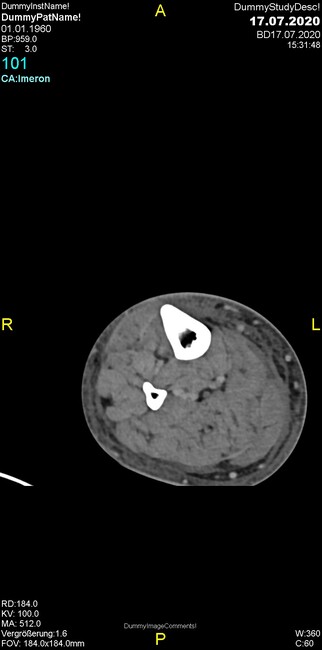

Um welche Modalitäten handelt es sich?

- Röntgen p.a. und lateral, CT coronar Knochenfenster, CT axial Weichgewebsfenster

- Röntgen p.a. und oblique, CT coronar Knochenfenster, CT axial Weichgewebsfenster

- Röntgen p.a. und lateral, CT sagittal Weichgewebsfenster, CT coronar Knochenfenster

- Röntgen p.a. und oblique, CT sagittal Knochenfenster, CT coronar Weichgewebsfenster

- Röntgen p.a. und lateral, CT coronar Weichgewebsfenster, MR axial

Was trifft auf den Befund zu?

- Der Befund beschränkt sich auf den Knochen.

- Es besteht hochakuter Handlungsbedarf.

- Der Befund ist tendenziell benigne.

- Der Befund ist tendenziell maligne.

- Der Befund weist einen Zusammenhang zum Patientenalter auf.

Was fällt in der CT im Knochenfenster auf?

- Mediale Gelenkspaltverschmälerung

- Dezente Erosion der fibulären Kortikalis

- Frakturspalt der lateralen Tibiametaphyse

- Weichgewebskalzifikationen lateral angrenzend an den Gelenkspalt

- Osteolyse der Tibiametaphyse unter Beteiligung der Kortikalis

Was kommt differentialdiagnostisch in Frage?

- Kompartmentsyndrom

- Osteomyelitis mit Weichgewebsanteil

- Metastase mit pathologischer Fraktur

- Rheumatoide Athritis

- Posttraumatische Verletzung